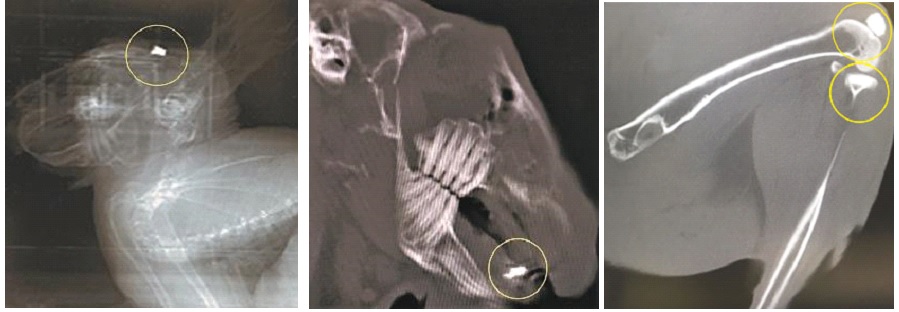

Фото: клинические испытания имплантатов из полученных биоматериалов. Источник: Евгений Папынов

Картинка: клинические испытания имплантатов из полученных биоматериалов. Источник: Евгений Папынов

Первые образцы протезов, изготовленные таким образом, специалисты имплантировали в лапы нескольких мышей. Как показали эти опыты, одна из двух версий нового материала не была токсичной и не вызывала воспаления и другие негативные последствия, часто характерные для имплантации уже существующих типов протезов. Вторая версия была менее удачной из-за хрупкости и наличия примесей, что было связано с низкой температурой их обработки.